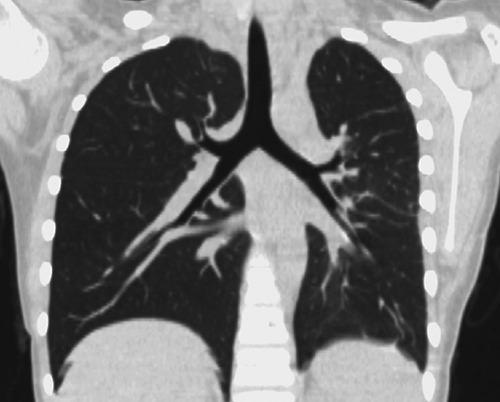

Inflammatory myofibroblastic tumor (IMT) belongs to the group of soft tissue tumor and could occur at any anatomical site from the central nervous system to gastrointestinal tract. The lung and abdomen are commonly affected sites, however, pulmonary IMT is predominantly located within the parenchyma rather than presenting as endobronchial lesion. IMTs may occur in any age group, but they are observed most commonly in children and adolescents. Here, we present a case of IMT arising from the left main stem bronchus in a 10-year-old girl.